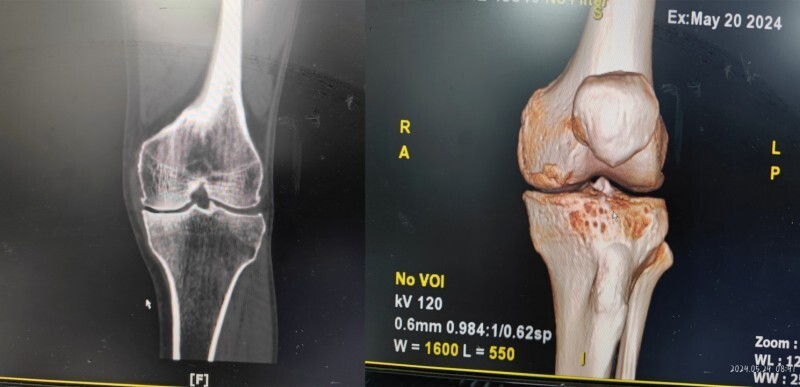

第1例:机器人辅助下全膝关节置换术

68岁的何先生因“左膝关节疼痛伴活动受限18年加重2个月”慕名来院就诊,经检查后手术治疗,经过仔细的术前评估,医生建议其选择机器人辅助下全膝置换手术,患者家属之前就在媒体上听说过机器人手术,考虑之后同意了手术方案。

23日上午9时许,手术开始,约2个半小时顺利完成手术,术后片子显示假体植入位置准确,目前患者各项情况良好。